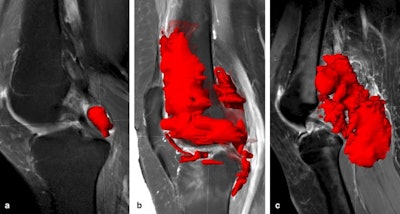

Emerging 3D MR segmentation techniques make it feasible to quantify tumor burden and provide a quick visual assessment of lesion distribution throughout the knee, but the process is time-consuming and operator-dependent, and more automation is needed, Dutch researchers have found.

Orthopedic surgeons and radiologists at Leiden University Medical Centre performed a first step towards objective volumetric quantification of diffuse-type tenosynovial giant cell tumor (D-TGCT) by segmenting 3D tumor volume in 40 treatment-naïve patients with D-TGCT. They published their preliminary findings in an article posted on 1 February by Insights into Imaging.

Volumetric quantification techniques integrated with deep learning methods may help measure tumor change, but developing such an automated quantification method is challenging due to irregular growth and heterogeneous signal intensity of TGCTs, they explained.

For 3D segmentation, the researchers used gadolinium-enhanced sagittal T1-weighted spectral inversion recovery (SPIR) and an axial T2 DIXON (water only) scan. Measuring tumor volume was done in Brainlab Elements, an application that is commonly used for preoperative planning of bone and soft-tissue tumors.